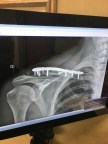

I had not thought of these things at all in years. Really. But while coming out of anesthesia from the surgery I had just a few short weeks ago to repair my collarbone, I felt my mother’s presence so strongly. It was overwhelming, a washing over my being. I felt a peace and a wink and nod. Okay, your okay. I’m okay, we’re okay. Okay?

h 9 screws and a metal plate in my right shoulder, it’s a wonder I can even function.